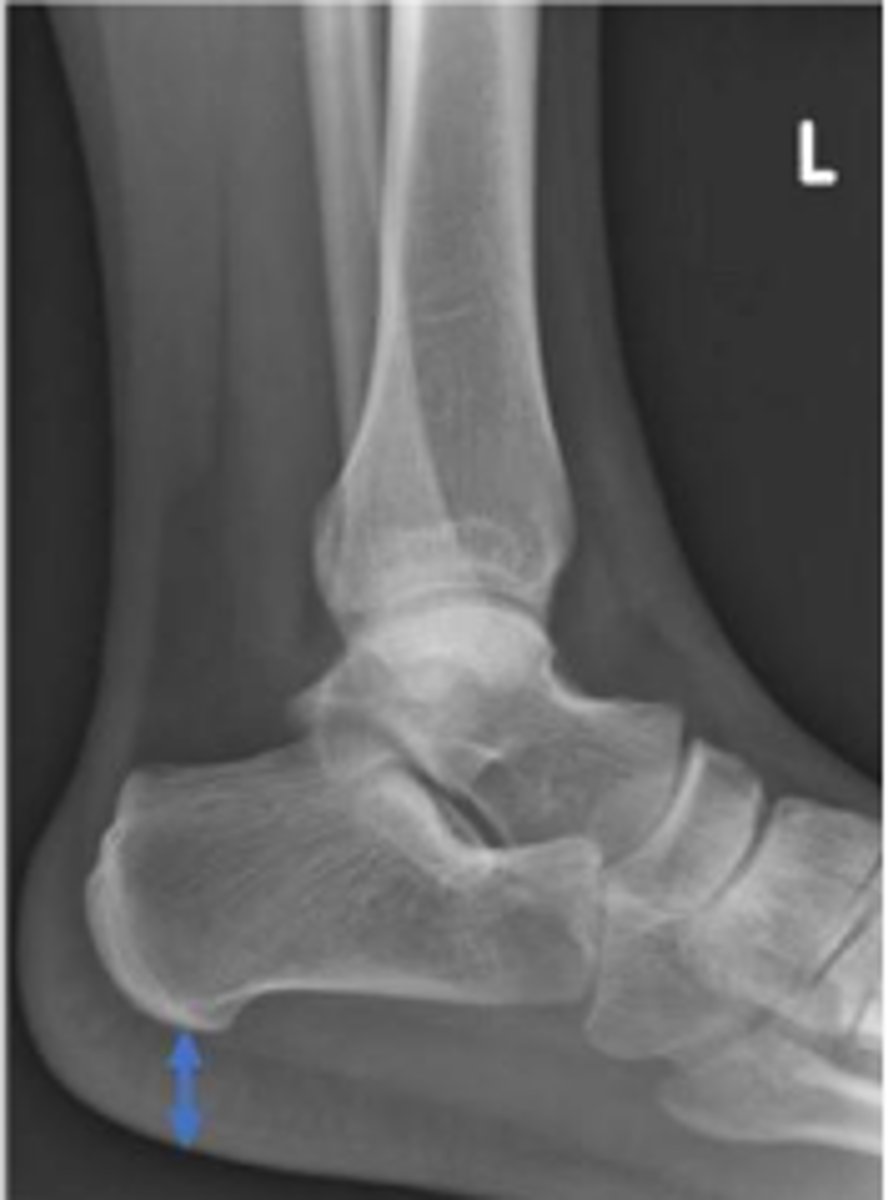

Heel pad measurement

What is the name of the assessment?

Females: average 19mm (maximum of 23mm)

Males: average 19mm (maximum of 25mm)

What is the normal range for the assessment?

Achille's tendon thickness

4-8mm

Yes

Is the assessment within normal limits?